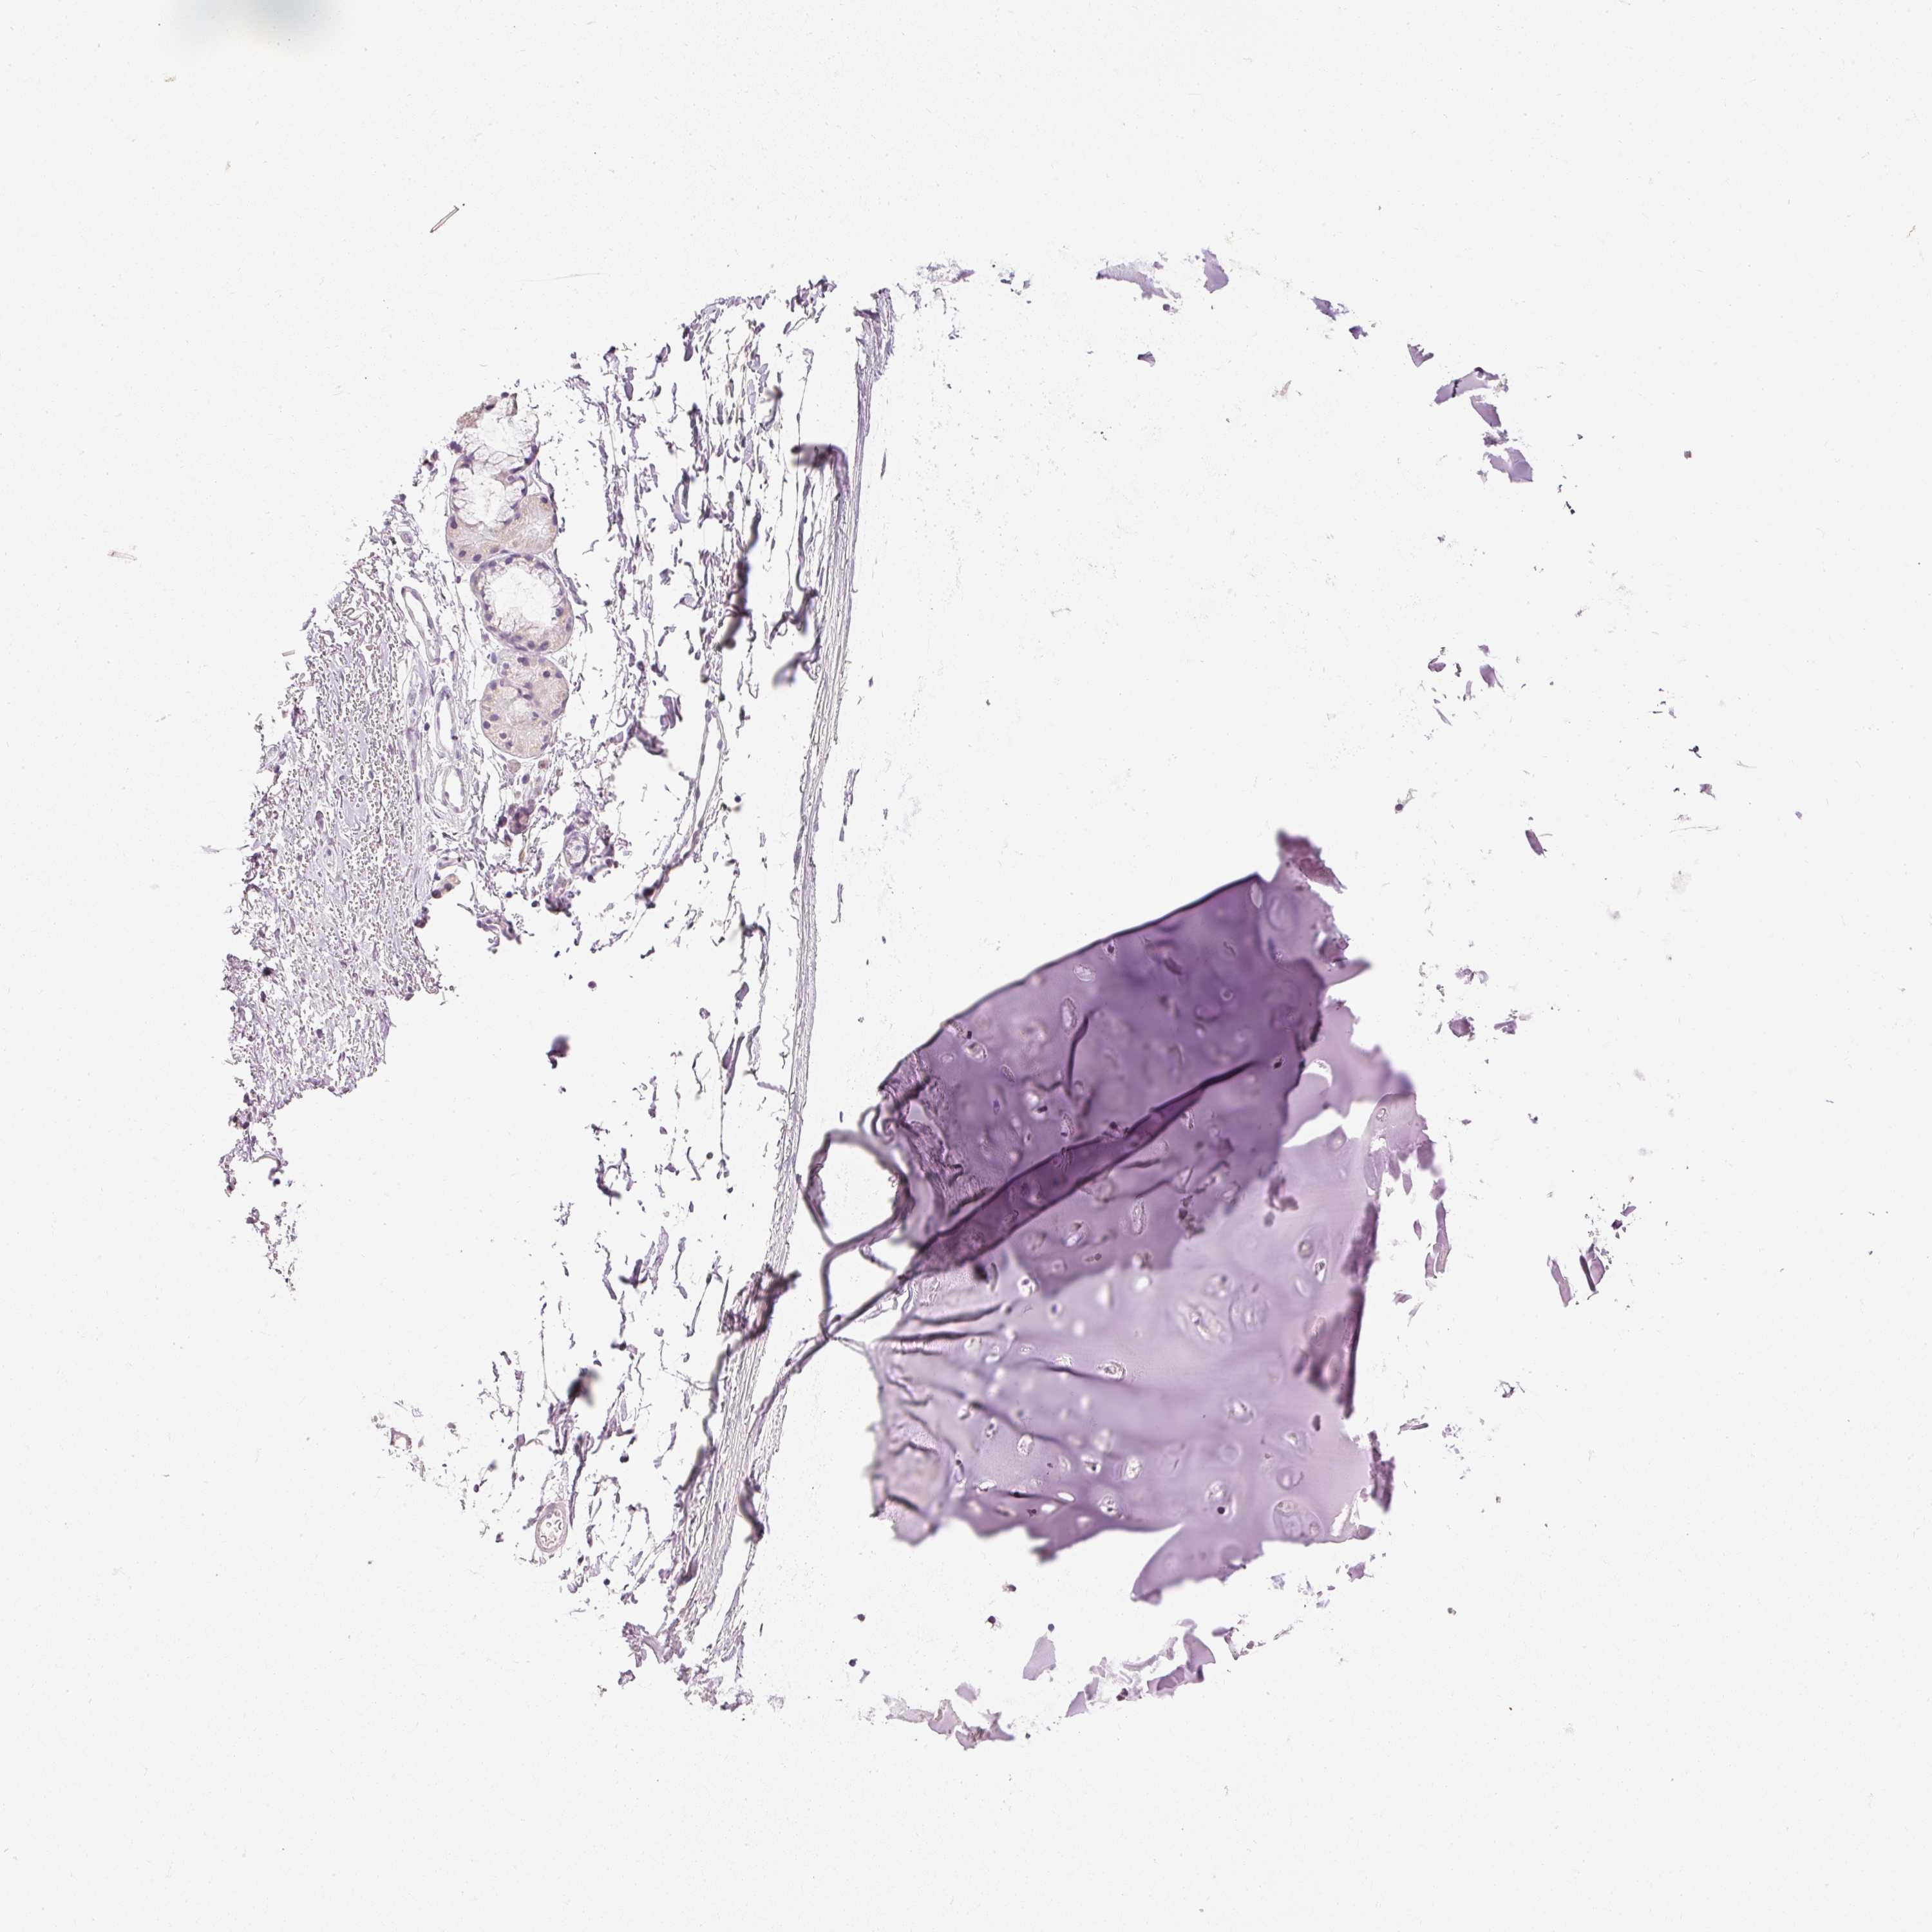

ADIPOSE TISSUE - Antibody stainingi

Antibody staining in the annotated cell types in the current human tissue is reported as not detected, low, medium, or high, based on conventional immunohistochemistry profiling in selected tissues. This score is based on the combination of the staining intensity and fraction of stained cells.

Each image is clickable and will lead to virtual microscopy that enables deeper exploration of all samples and also displays staining intensity scores, fraction scores and subcellular localization as well as patient and tissue information for each sample.

Antibody CAB013066

Adipocytes Not detected